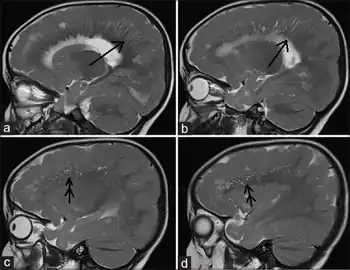

a, b)MRI shows radial stripes arrow c,d) show scattered dots in form of hyperintensities arrow

Pachygyria arrow

Different imaging modalities are commonly used for diagnosis. While computed tomography (CT) provides higher spatial resolution imaging of the brain, cerebral cortex malformations are more easily visualized in vivo and classified using magnetic resonance imaging (MRI) which provides higher contrast imaging and better delineation of white and gray matter.[7]

Diffuse pachygyria (a mild form of lissencephaly) can be seen on an MRI as thickened cerebral cortices with few and large gyri and incomplete development of the Sylvian fissures.[3]